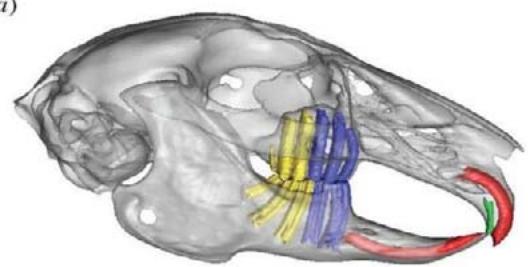

A dentição dos coelhos é o tipo heterodonte, todos os dentes são elodontes (crescem por toda a vida) o número de dentes é 28 e tem fórmula dentária: I2/1, C0/0, P3/2, M3/3. O músculomasseter é o principal músculo da mastigação; o músculo temporal é pequeno; portanto, o processo coronoide é pequeno; o crânio é fenestrado; existem grandes processos semelhantes a asas nos ossos frontais; há um grande forame incisivo; há uma ponte palatina entre os pré- molares formados por porções dos ossos maxilar e palatino; possuem grandes bolhas timpânicas EMILY, Peter (2021). A mandíbula superior do coelho contém três pré-molares e três molares, enquanto a mandíbula inferior possui dois pré-molares e três molares através da visualização das raízes dosdentes a partir dos dados de micro tomografia computadorizada observou-se que os pré-molares da mandíbula têm raízes predominantemente orientadas verticalmente (Fig. 1). Em comparação, enquanto as raízes molares na maxila também são verticais, elas têm uma orientação mais posterolateral na mandíbula. WATSON, Peter J. (2014). A altura média da coroa dos incisivos mandibulares e maxilares em coelhos domésticos adultos é de 6,0 mm. A profundidade de sondagem periodontal saudável normal dos incisivos inferiores em coelhos é de 5 a 6 mm. Os pré-molares e molares são agrupados como uma unidade funcional com uma superfície oclusal relativamente horizontal com dobras transversais de esmalte para triturar e picar alimentos fibrosos difíceis. As dobras de esmalte correspondem à invaginação profunda do esmalte no lado palatino dos dentes da bochecha maxilar e no lado vestibular dos dentes da bochecha mandibular. As dobras do esmalte são preenchidas com material semelhante ao cemento e são visíveis do lado de fora como sulcos de desenvolvimento. O esmalte periférico é mais espesso nas superfícies linguais dos dentes maxilares e nas superfícies vestibulares dos dentes maxilares. O músculo masseter é muito maior que o músculo temporal, e o processo coronóide é pequeno em comparação com o dos carnívoros (como uma adaptação da ingestão de alimentos fibrosos e duros). A oclusão é anisognata - o arco maxilar é mais largo que o arco mandibular. O plano oclusal é inclinado aproximadamente $10 ^ { \circ }$ em direção à horizontal. A forma da articulação temporomandibular permite principalmente movimento lateral considerável, mas muito pouco movimento rostrocaudal. Os incisivos inferiores ocluem entre o primeiro e o segundo incisivos superiores VESTRAETE, Frank (2005).

(1) Fonte: rsif.royalsocietypublishing.org J. R. Soc. Interface 11: 20140564 F Visualização da raiz do dente molar e incisivo através dos dados da microtomografia computadorizada: vista laterale oblíqua; (b) close-up das raízes dos dentes da mandíbula. Os pré-molares (azul) têm raízes predominantemente orientadas verticalmente, enquanto os molares (amarelo) têm uma orientação mais pósterlateral.